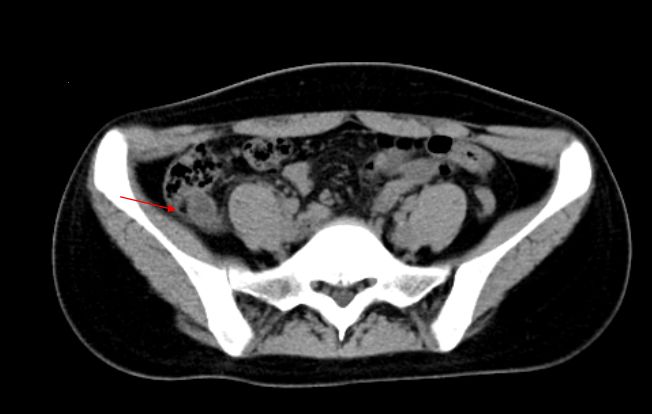

CT是其最具价值的影像检查手段。急性阑尾炎主要表现为阑尾增粗肿大,壁增厚,腔内积液积气和粪石,阑尾周围脂肪密度增高,少量积液,腹膜增厚。如出现肠腔外气体、肠腔外粪石及增强扫描阑尾壁缺损需诊断穿孔。

急性阑尾炎:CT平扫,阑尾增粗肿胀,腔内可见高密度粪石,阑尾浆膜面模糊,周围少许渗出。